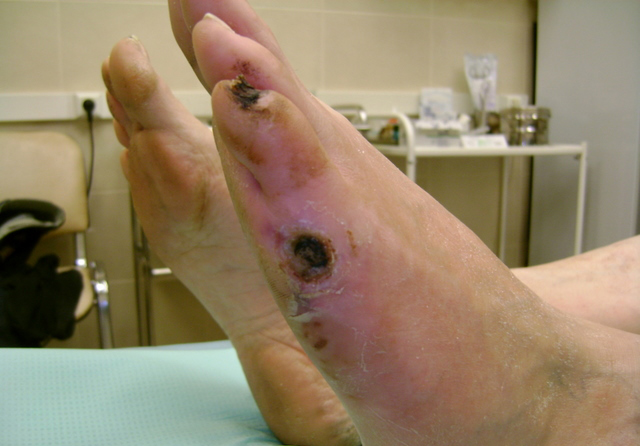

При данном заболевании периодически наблюдаются острые и хронические воспалительные процессы, а также тромбоз артерий и вен в руках и ногах. Главным признаком является боль в пораженных участках, которая проявляется как в состоянии покоя, так и при ходьбе, что приводит к хромоте. Изменения в кровообращении увеличивают чувствительность к холоду. Периферические импульсы могут быть снижены или отсутствовать. Также наблюдаются изменения цвета конечностей, который может варьироваться от голубого до красновато-синего. Кожа становится тонкой и блестящей, а рост волос замедляется. Частыми осложнениями являются изъязвления и гангрена, что может привести к ампутации пораженной конечности.

- Болезненные открытые раны на конечностях.

Санация необходима при наличии некротических язв. В случаях гангрены часто требуется удаление пораженной ткани. Ампутация выше или ниже колена требуется лишь в редких случаях. Стрептокиназа может использоваться в качестве лекарственной терапии после радикальных операций в некоторых ситуациях.